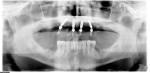

After 2 months of healing, the patient presented for assessment of osseointegration (Figure 13). All four implants were successfully osseointegrated and the patient was pleased with the function and esthetics of the provisional prosthesis. At the same visit, the conversion prosthesis was evaluated for proper fit, clinically, visually, and radiographically, and the multi-unit abutments were torque-tested to ensure they were not loose (Figure 14). The extraoral reverse scan technique, as described above, was used for the digital acquisition of the implant positions to allow CAD/CAM fabrication of a prosthesis prototype (Figure 15). The STL files from the extraoral reverse scan technique were imported into CAD software (exocad), and the prosthesis prototype was designed and milled. Additionally, a CAD/CAM verification jig was designed and milled to be tried-in simultaneously with the prototype to ensure quality control, as described above.15